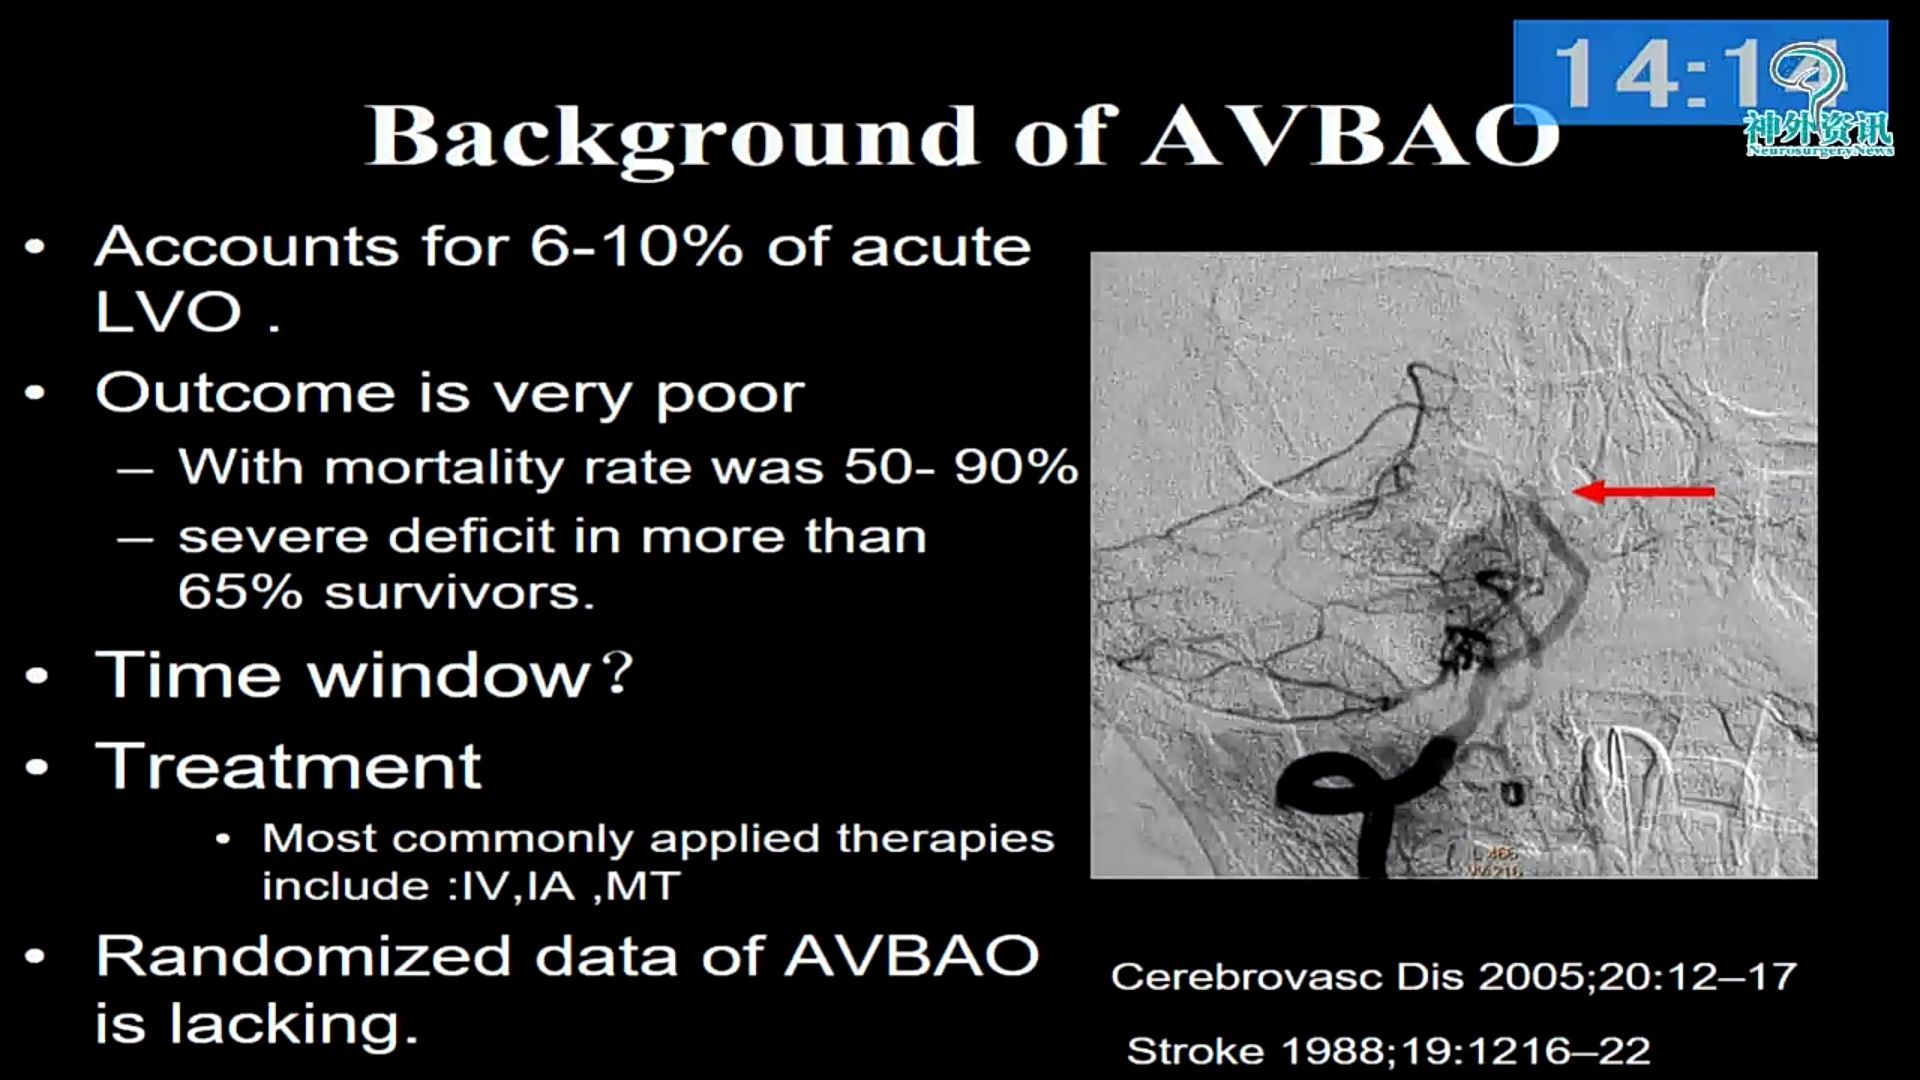

急性椎基底动脉闭塞血管内治疗